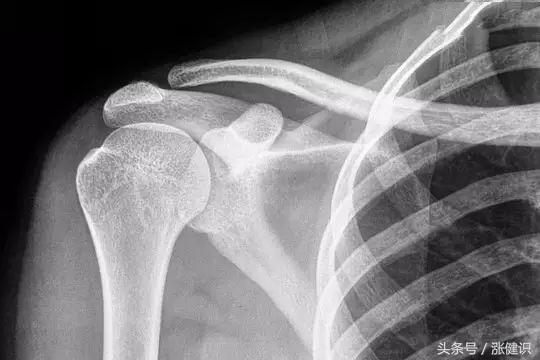

答案很明确,药物无法消除骨刺。骨质增生,俗称“长骨刺”。随着老年人免疫系统机能的逐渐下降,软骨的代谢功能、含水量也随之下降,关节的退变磨损会造成关节软骨损伤,从而继发关节周围的骨质增生。

说白了,骨刺就是增生的骨质,是关节软骨退化后多长出来的骨头,所以骨刺也是骨头。如果说有药物能溶解骨刺,那肯定也把旁边的骨头一起溶掉了。

了维持血液中钙浓度正常需要量,机体内部会自主进行调整,通过血液运输,从我们的骨骼及牙齿中,“借出”一些钙到血里维持血钙的平衡,弥补机体所需,这时我们会从X光片中看到骨质疏松的表现,但血中钙的含量往往正常。